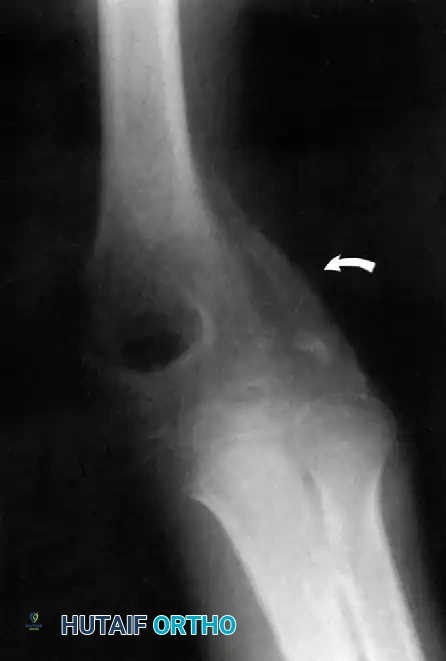

Furthermore, Allende and Freytes identified a pathognomonic radiographic and anatomical feature known as the "radial humeral horn," which was present in 100% of their 35 reported cases.

Fig. 58-23 Anteroposterior radiograph showing lateral dislocation and the characteristic horn of ossification. (From Bruce C, Laing P, Dorgan J, et al: Unreduced dislocation of the elbow: case report and review of the literature, J Trauma 35:962, 1993.)

This "horn" is the direct result of the ossification of a fracture hematoma trapped between the stripped periosteum and the joint capsule near the radial head. Recognizing this structure preoperatively is critical, as it must be surgically excised to achieve concentric reduction.